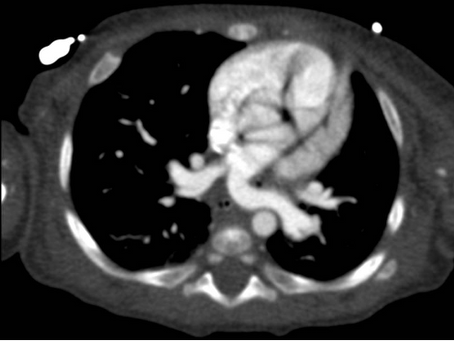

Caso del Mes: Sling de la Pulmonar – Junio 2022

1. BREVE HISTORIA CLÍNICA Lactante de 4 meses, producto de un embarazo controlado sin complicaciones. Desde el nacimiento con estridor...